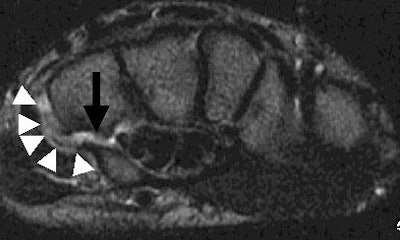

T2-weighted images with fat suppression are also very helpful in demonstrating the bone marrow and soft-tissue edema that is associated with an acute fracture. Coronal images, often obtained in MR imaging of the wrist, are limited in their ability to display most fractures of the hook of the hamate, due to the coronal orientation of most of these fractures.

| Above, an axial T2-weighted MR image shows the oblique fracture through the base of the hook of the hamate with intervening fluid (black arrow). The increased T2 signal, indicative of edema and inflammation (white arrowheads) corresponded to the location of the patient's pain. |